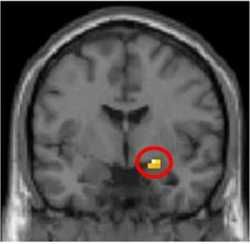

Zmysel pre spravodlivosť nám diktuje mozog Životný štýl

Zmysel pre spravodlivosť nám diktuje mozog

V ľudskom mozgu je zabudovaný mechanizmus, automaticky spúšťajúci zápornú reakciu, ak sa niekto odmietne spravodlivo rozdeliť